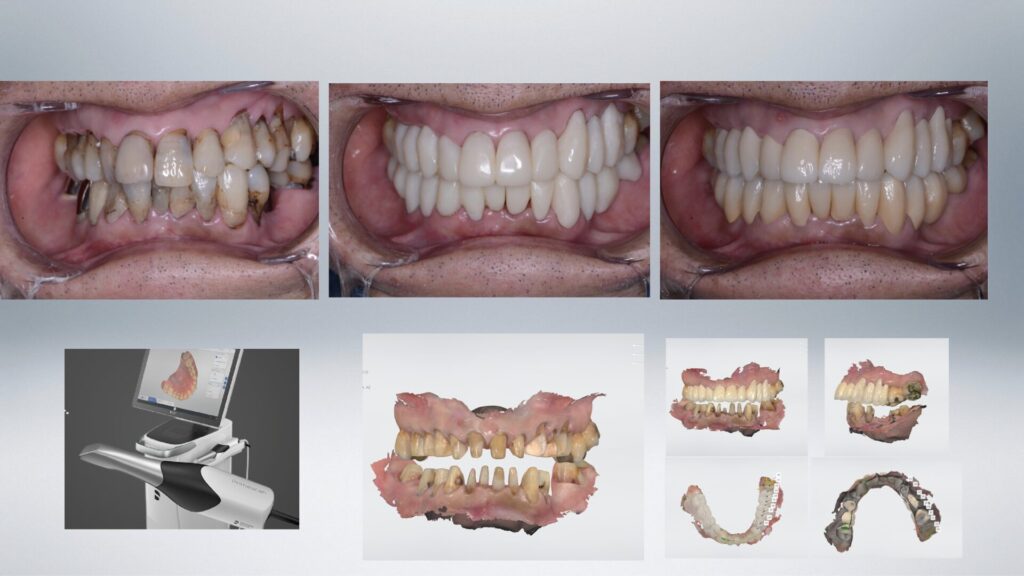

Before

After

| 診断名 | 全顎的う蝕(主に棍面う蝕、歯肉縁下う蝕) |

| 治療方法 | 誤嚥防止のためラバーダム下にてブロックごとに治療を進めたあとデジタル機器を応用し、仮の歯の製作を行なった。その後仮の歯での噛み合わせ、清掃状態の確認後最終的なセラミック修復を行なった。 |

| 備考 | 食道がんの既往があり歯を削った際の水の誤嚥や通常の歯型をとる行為が不可能な方でした。家族の紹介により遠方より来院。 デジタル機器を応用することで全顎的な治療を終えられました。 |